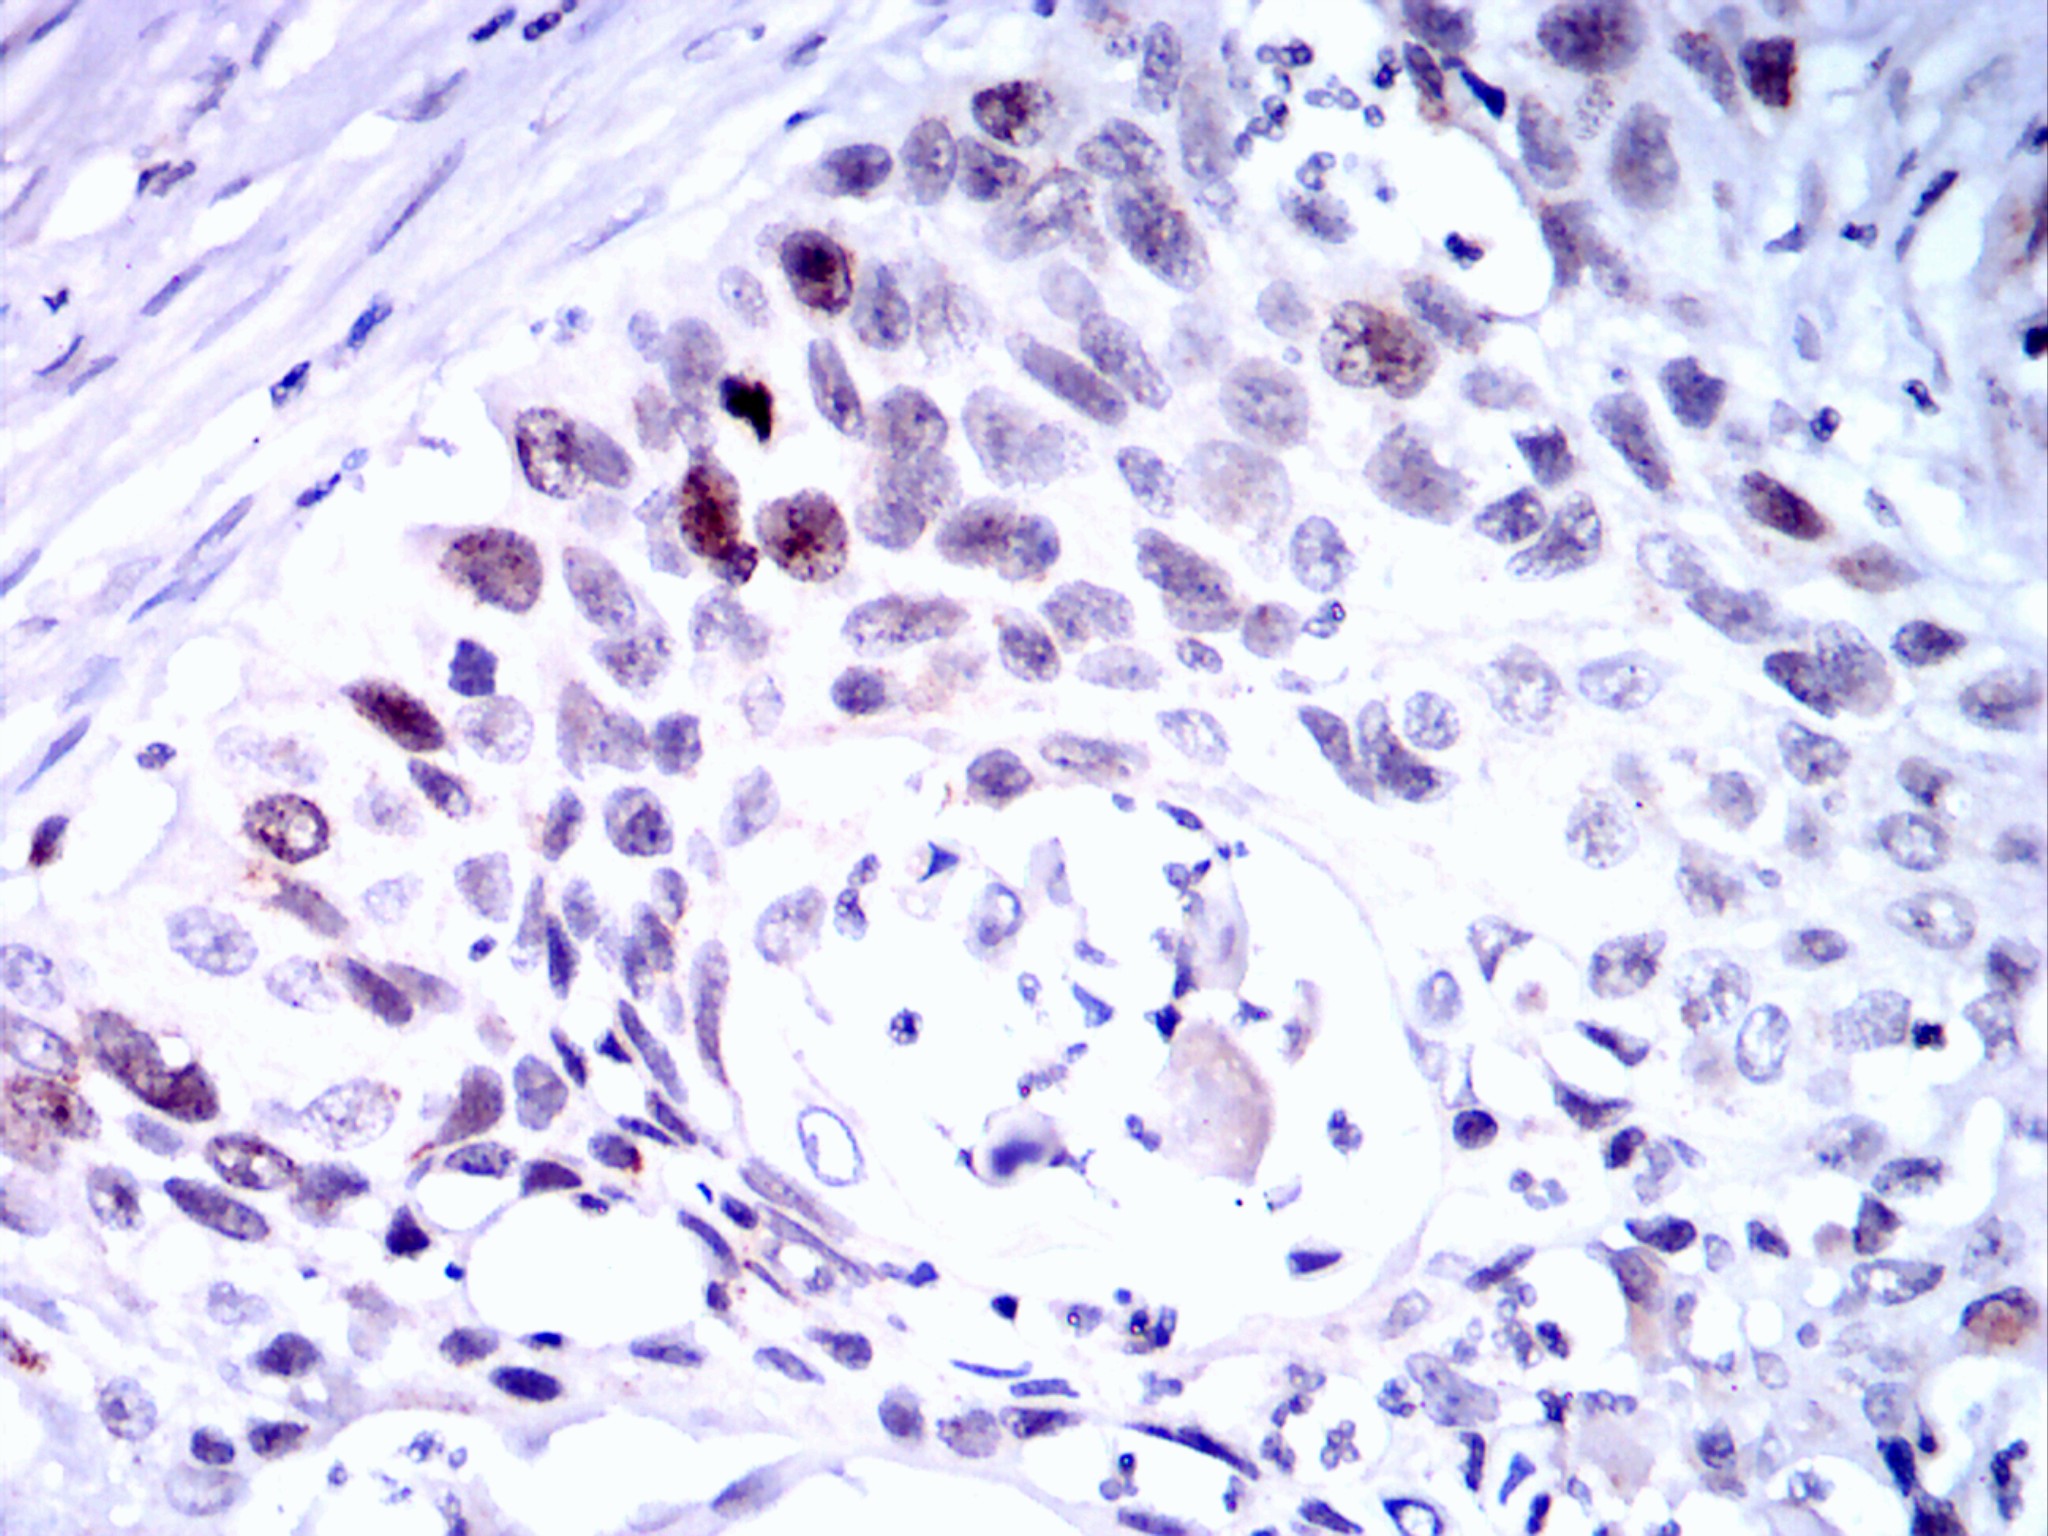

分类: 科研抗体货号: 20075别名: SRAP; STRAA1应用: IHC反应种属: Human

分类: 科研抗体货号: 20074别名: SRAP; STRAA1应用: IHC反应种属: Human